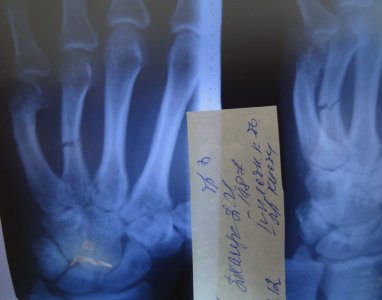

После этого я отходил 5 недель со дня репозиции, сняли лонгету, и сделали снимок:

Доктор сказал что сращения нету вообще, опять наложилли лонгету и сказал ходить ка минимум еще две недели только согнули пальцы немного под углом и уже на 3,4 и 5 палец плюс назначил магнитотерапию (вроде так, точно не помню) , вот фото лонгеты: